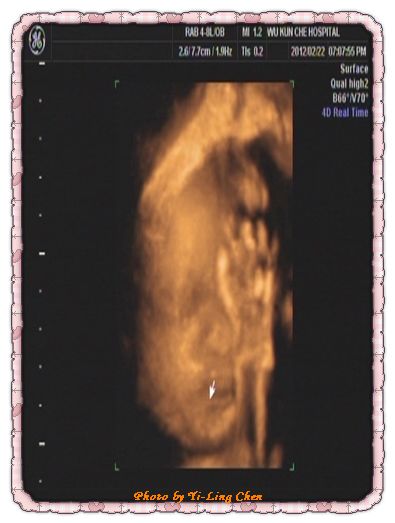

這是在睡覺,用手遮了半張臉的土豆寶貝

老實說~~第一眼看到這張超音波,我的第一個反應是~~怎麼這麼像“孟芃姊姊”呀!

不過,土豆有跟我一樣厚厚的嘴唇喔!

回家一直看這一張超音波

總覺得,土豆鼻子以下好像一個人喔!

一直看一直想~~終於讓我想到了

土豆這側邊臉像我家老哥呀!也就是像土豆的舅舅啦!

哈哈哈~~

真的想不到土豆竟然有像舅舅呀!